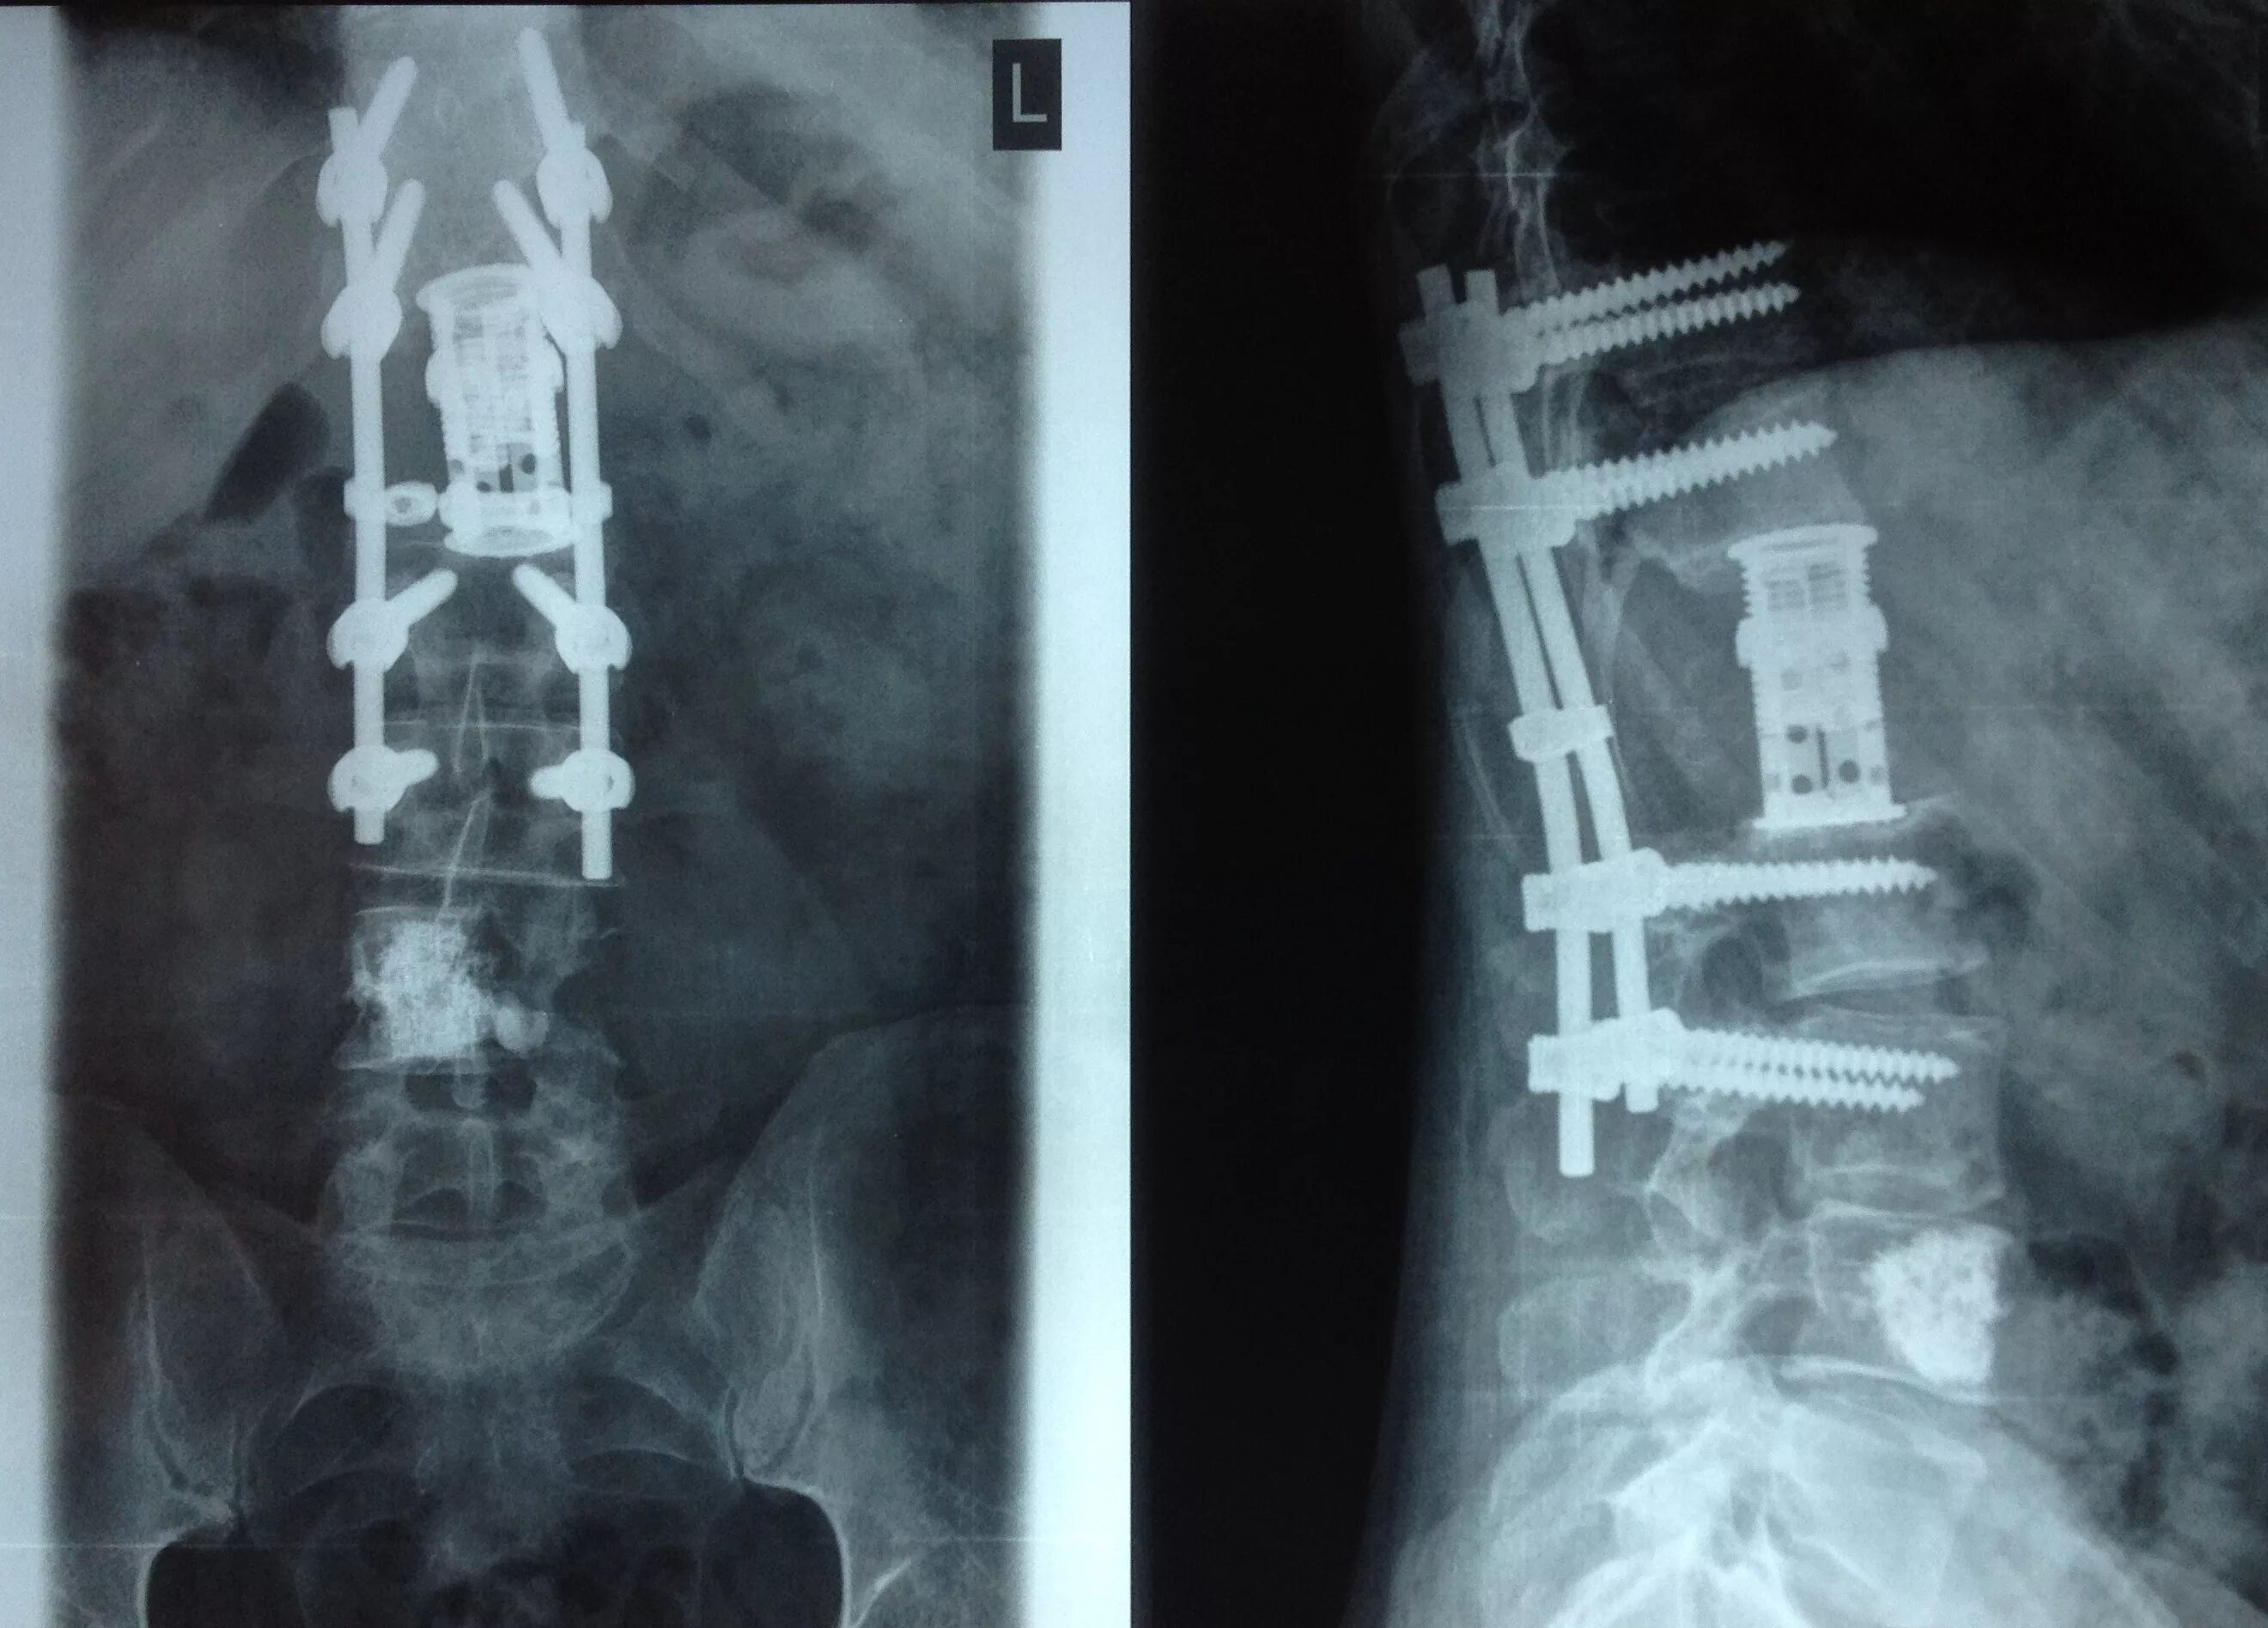

Операция на пояснично крестцовом отделе позвоночника